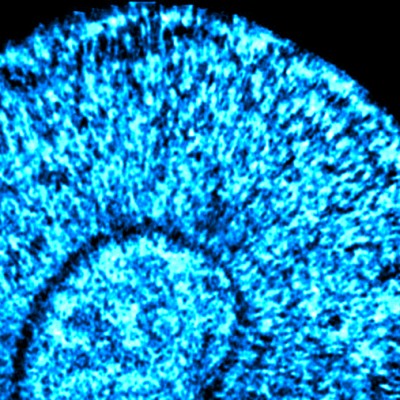

The identification of various genetic susceptibility loci associated with neurodegenerative diseases, such as Frontotemporal Dementia, opens up new possibilities for understanding the pathogenic mechanisms associated with the disease. In this project, we develop induced pluripotent stem cell lines (CMPi) from blood cells of patients that carry allelic variants in genes of interest. We used the CRISPR-Cas9 gene editing system to generate cells identical to the original ones with the corrected mutation. Through the directed differentiation of these cells to neural lineages in 2D culture systems, together with the technology to generate three-dimensional structures called “brain organoids”, we seek to identify in human models how pathogenic variants contribute to the initiation and progression of Frontotemporal Dementia. Since age is a main risk factor in the development of dementias, we are interested in elucidating the role of molecular pathways associated with aging in disease development. This knowledge will contribute to the identification of potential therapeutic targets to prevent or treat the disease.